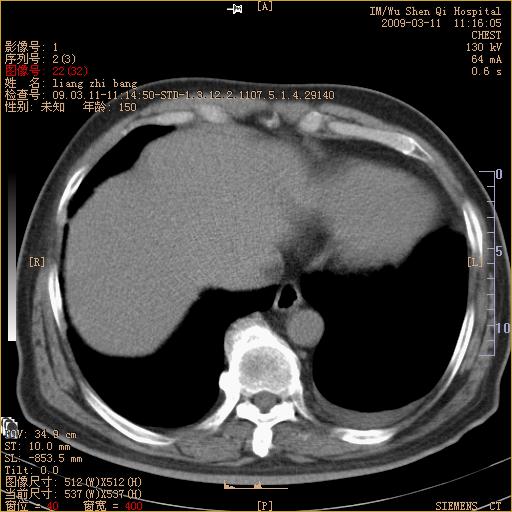

标题: CT18604:男,60岁,咳嗽一月余 [打印本页]

标题: CT18604:男,60岁,咳嗽一月余

1)考虑左肺上叶中央型肺癌并左肺上叶肺不张;建议必要时行纤支镜检查进一步明确诊断。2)左侧胸腔积液。

肺门肿块、支气管开口闭塞伴肺不张及胸水!典型的中心型肺癌变现!

1、左肺上叶中央型肺癌并上叶阻塞性肺不张。

2、左侧胸腔少量积液,右侧胸膜轻度增厚。

左肺们肿块并左肺上叶不张。考虑左肺中心性肺癌并左肺上叶不张及左侧胸腔积液